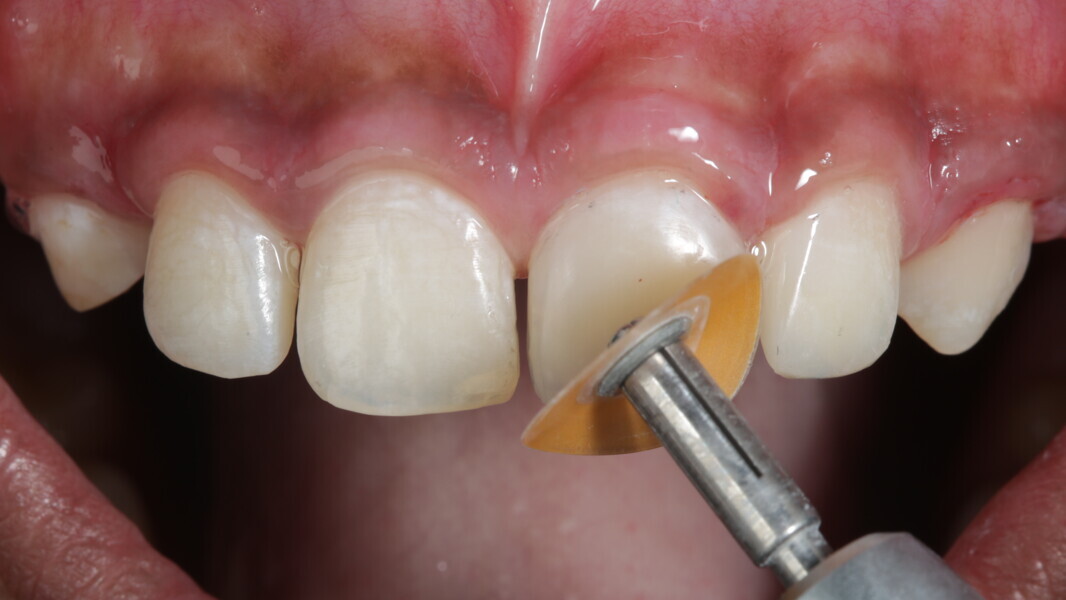

Fig 31-41: Polishing protocol and post-op